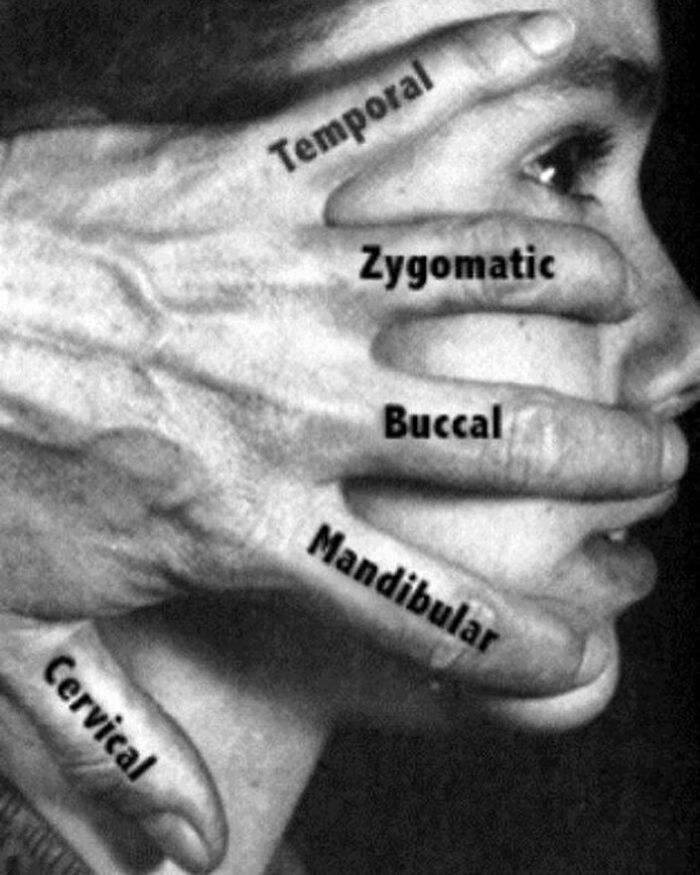

The facial nerve is the seventh cranial nerve, or simply CN VII. It emerges from the pons of the brainstem, controls the muscles of facial expression, and functions in the conveyance of taste sensations from the anterior two-thirds of the tongue. The nerves typically travels from the pons through the facial canal in the temporal bone and exits the skull at the stylomastoid foramen.

The facial nerve has five main branches, although the anatomy can vary somewhat between individuals. The branches are, from top to bottom: frontal (or temporal), zygomatic, buccal, marginal mandibular, and cervical. Each of these branches provides input to a group of muscles of facial expression.